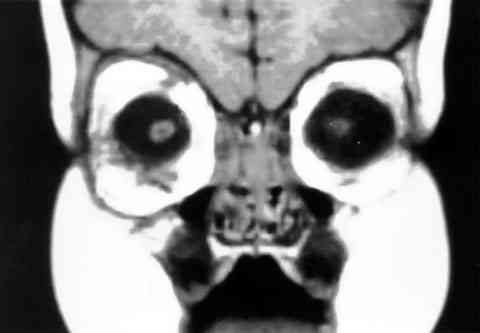

Figura 5

RESONANCIA NUCLEAR MAGNÉTICA EN T1, CORTE CORONAL CON NORMALIZACIÓN DEL TAMAÑO ORBITARIO TRAS TRES MESES DE LA EXTIRPACIÓN DEL QUISTE COLOBOMATOSO.